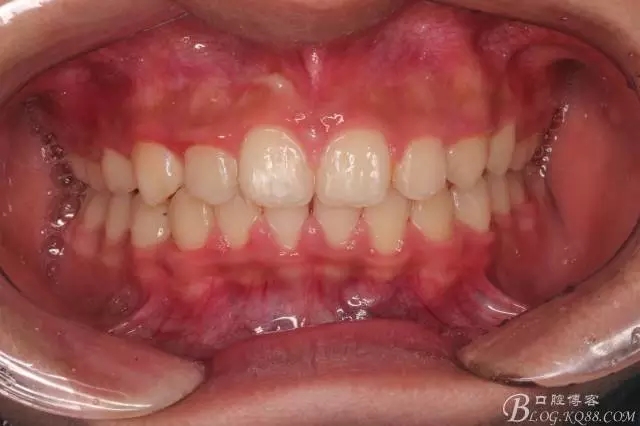

一晃快兩年了,我覺得關節(jié)重建及咬合穩(wěn)定,再加上患者的急迫愿望,我們拆除了矯正器。

尖牙關系中性,磨牙關系中性,咬合鎖結(jié)良好!

15歲了,1米78的個頭,陽光帥氣的他,側(cè)貌堪比天安門國旗手的面型?。釘懒耍?/p>